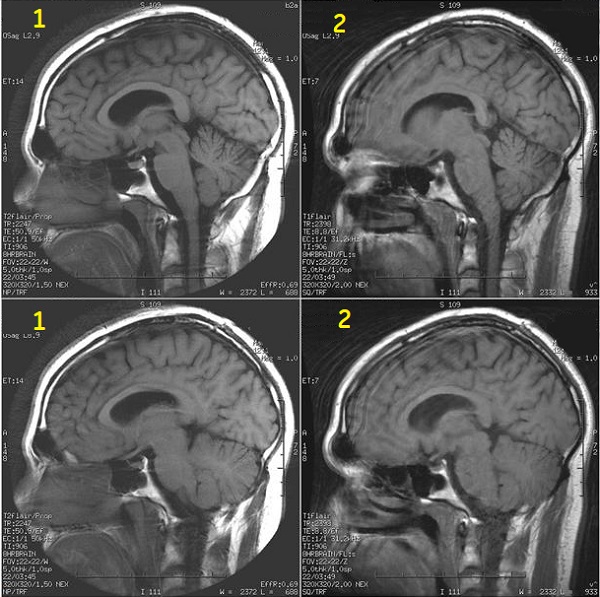

Figure 2. Image comparison demonstrating reduced flow artifact and improved gray/white matter contrast.

Table 2. Image legend

NumberDescription

1SE images

2PROPELLER post contrast images